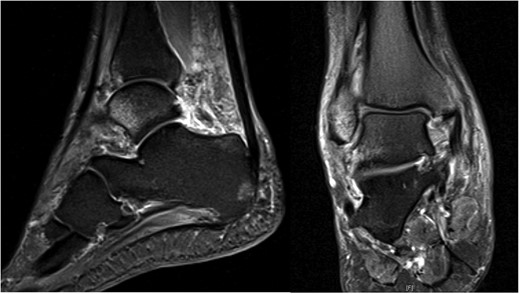

A 30-year-old male patient presented to Emergency Department (ED) following a run over injury. The patient described the mechanism of injury as moving his body over his run over foot. On clinical examination, there was obvious deformity and swelling of the right ankle. Dorsalis pedis pulse was felt but weak compared to the contralateral side with a capillary refill time under 3 s. The posterior tibial artery could not be palpated because of the deformity. X-rays showed posterior ankle dislocation without associated fractures (Fig. 1). Urgent reduction of the dislocation was done under sedation in ED. The knee was first flexed to relax the tendon Achilles then longitudinal traction with gentle forward force applied to the heel with immediate reduction of the deformity achieved. The foot was reassessed for vascular status. Triphasic pulse in both drosalis pedis and posterior tibial artery was detected with hand held Doppler. Ankle was immobilized in posterior below knee back slab to accommodate for swelling and check x-rays confirmed reduction of the ankle joint (Fig. 2). CT scan was done afterwards to define any subtle incongruity or osteochondral fragments entrapped in the joint. CT did not show any associated fractures and showed congruent reduction of the ankle joint (Fig. 3). Patient was mobilized touch weight bearing for first 2 weeks. The back slab was changed for weight bearing short leg cast and progressive weight bearing was allowed for the following 4 weeks. At 6 weeks follow up, plaster was removed and on examination patient still had moderate tenderness over the medial joint line and deltoid ligament area. Also, patient had limited range of plantar and dorsal flexion. Referral for physiotherapy was done for start of functional rehabilitation and range of motion exercises and in mean time MRI was done to delineate extent of ligamentous injury. MRI showed bone bruising of the lateral malleolus, medial malleolus and lateral talus (Fig. 4). The anterior talufibular ligament (ATFL), calcaneofibular ligament (CFL), posterior talofibular ligament (PTFL) and deltoid ligaments were sprained but intact. At 12 weeks follow up, patient could walk normally without any symptoms of instability and achieved 20° of both plantar and dorsal flexion. At 16 weeks, patient achieved full range of motion of ankle and was able to return to work. At 24 weeks follow up patient was able to resume his sport activates as preinjury level.

T2 MRI images showing high signal in medial malleolus, lateral malleolus and talus signifying bone bruise.